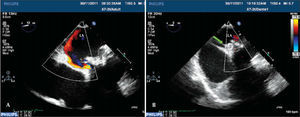

– Three-dimensional transesophageal echocardiogram images obtained sequentially during the procedure. In A, the periprosthetic defect (green arrow), which is located at the 3 o’clock position with the heart in anatomical position. In B, the unsuccessful attempt to go past the periprosthetic defect with the catheter, which actually passed through the central orifice of the prosthesis. In C, the catheter after going past the periprosthetic defect (red arrow). In D, two Amplatzer™ Vascular Plug III devices are already released, closing the periprosthetic defect (yellow arrows).

– Conventional transesophageal echocardiography images. In A, the periprosthetic defect with regurgitation into the left atrium. In B, after the Amplatzer™ Vascular Plug III (green arrow) device implantation, which is located between the prosthetic ring and the atrial wall, defect occlusion with the disappearance of periprosthetic regurgitation. LA=left atrium.